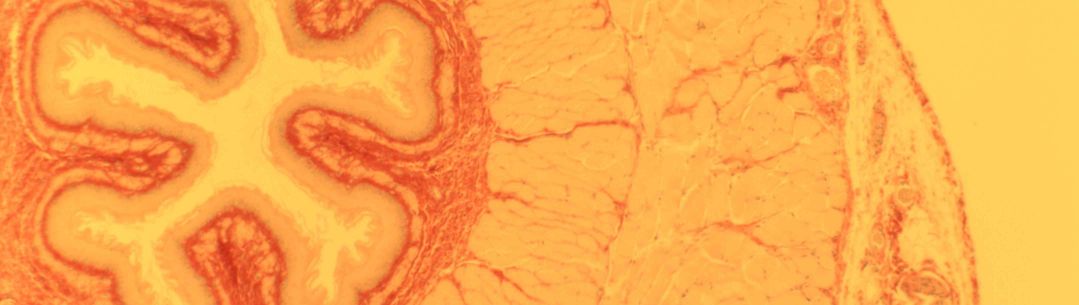

In this project, we are designing a bio-inspired implant that will serve as a novel treatment for obesity. The aim is to target the vagus nerve which transmits information between the gut and the brain. By stimulating the vagus nerve with electrical impulses, the implant will mimic the natural satiety signals produced after a meal, providing the patient with a means of appetite control.

By studying the role of the vagal system in the control of energy metabolism - understanding which nerve signals suppress or elicit food satiety - we can design efficient treatments for obesity.

We aim to develop an accurate system for detection, stimulation and recording of chemical and electrical changes in the vagus nerve in response to physiological stimulation of gut hormones and nutrients.